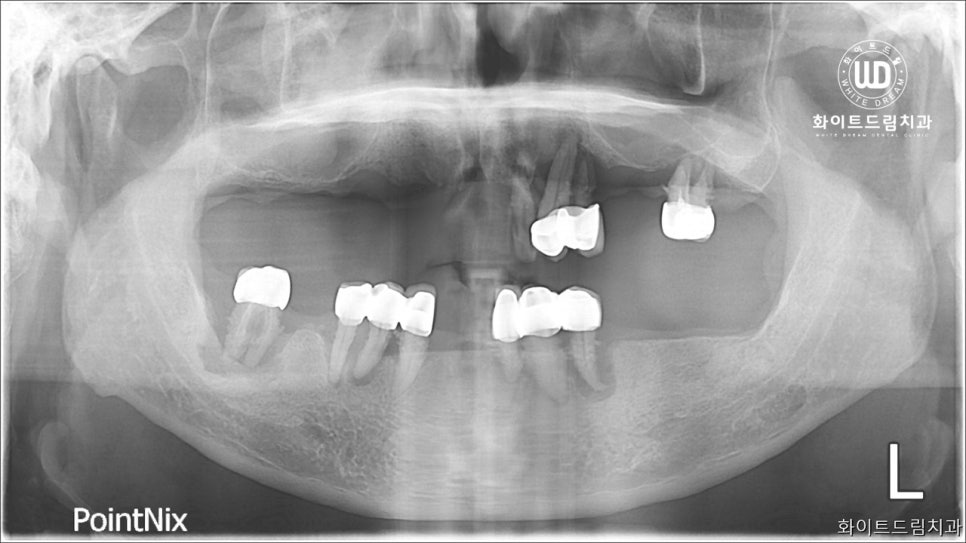

이번에 저희 치과에 내원해주신 환자분께서는 기존에 진료를 받아 부분틀니를 사용하고 계셨으며. 남아있는 치아 마저 전부 흔들려 불편함이 지속된다고 말씀해주셨는데요. 앞서 설명해 드린 대로 잇몸과 치아 사이에 염증과 출혈이 심하여 제 기능을 하지 못하는 상태이셨습니다.

사진상으로 보시면 부분틀니를 오랫동안 사용하시면서 골 소실이 많고, 잇몸과 잇몸 뼈 주변까지 염증이 진행된 상태셨습니다. 전반적으로 구강 내 염증 정도가 심했고, 오랜시간 치아가 소실되어 있어 잇몸뼈 또한 녹아내린 상태였습니다.

이전의 케이스와 비슷하게 기존 보철물들은 제거가 필요한 상태였는데요. 환자분 동의 하에 남은 치아 전체 발치 후 상악 양측 구치부 상악동 거상술 및 뼈이식 진행 후 임플란트를 식립하는 임플란트 치료과정을 적용한 사례입니다.

상악동은 코 옆에 위치하고 하방으로는 위 어금니 치조골이 존재합니다. 하지만, 나이가 들어감에 따라 아래로 내려와 치조골 양이 조금씩 줄어들게 되는데요. 이러한 이유로 위턱의 작은 어금니와 큰 어금니가 빠진 경우 임플란트를 심을 치조골이 부족한 경우가 많습니다.

즉, 임플란트를 심을 뼈가 부족한 상태인 것을 확인할 수 있었습니다. 내원해주신 환자분께 상악동 점막을 들어올려 생긴 공간에 뼈를 이식하여 임플란트를 심을 수 있도록 도와드렸습니다.